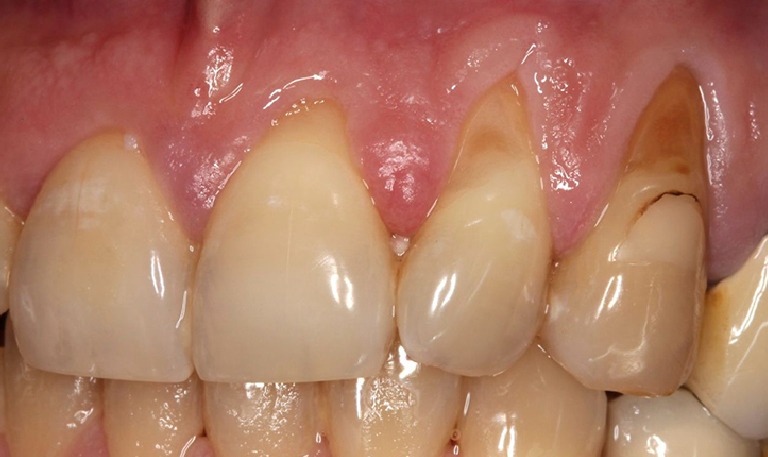

Injerto de encía para solucionar recesión

BeforeAfter